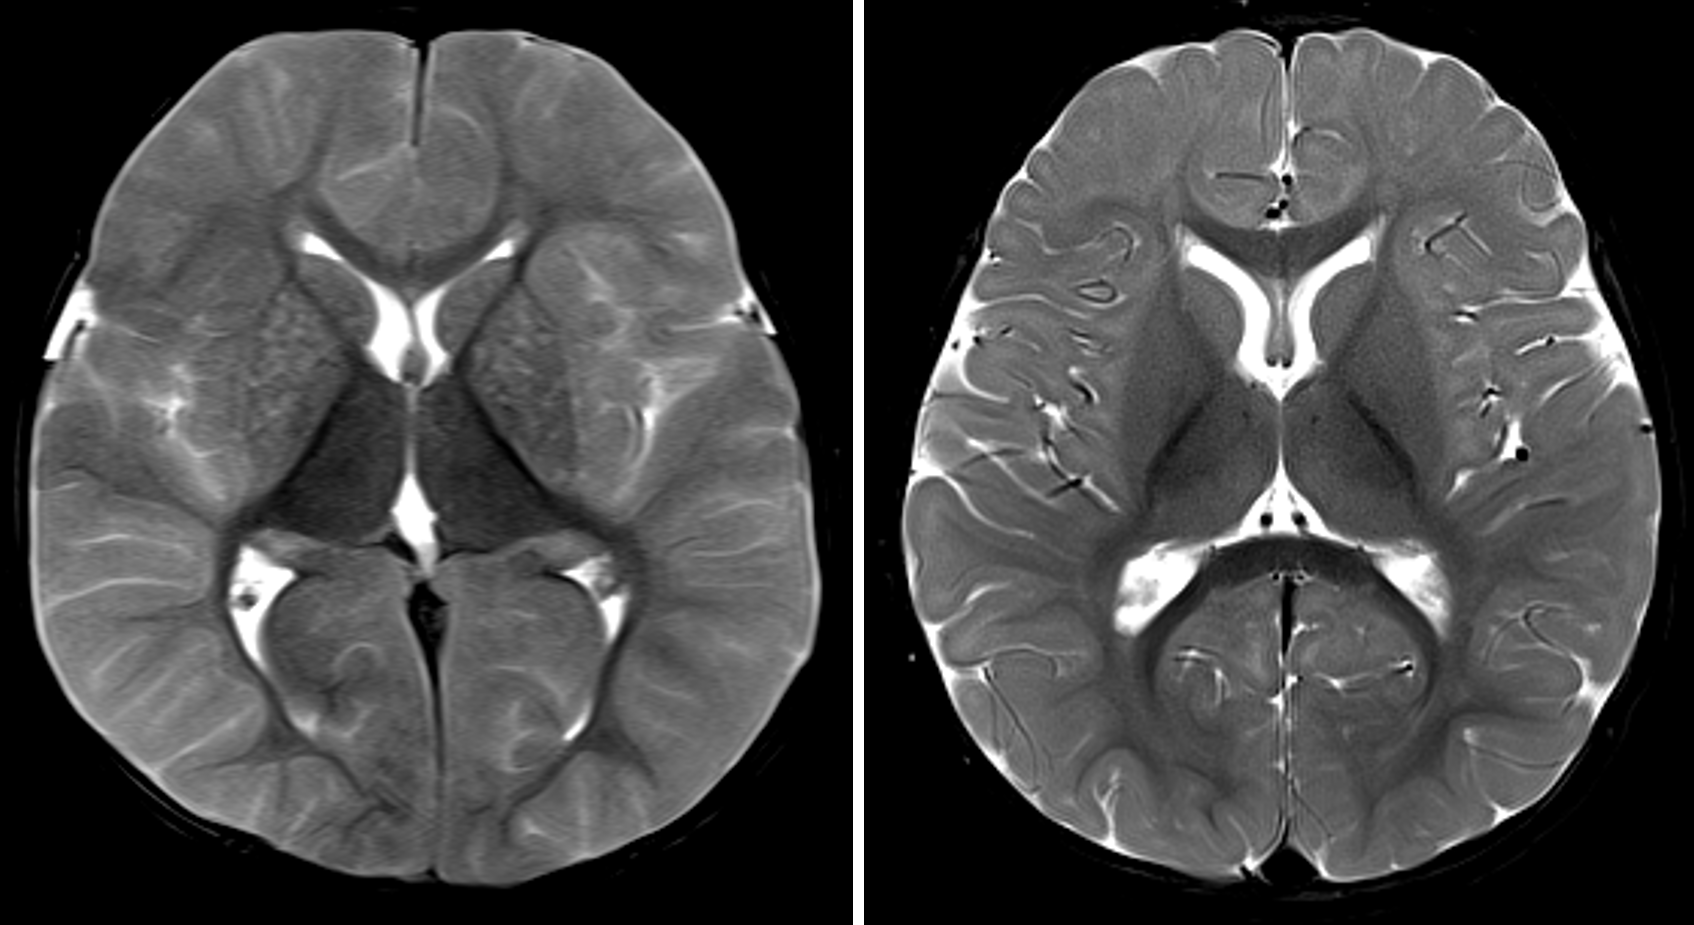

34+ Hypoxic Brain Injury At Birth Pictures. In today's educational video we will discuss the difference between an anoxic and hypoxic brain injury at birth. Imaging findings from birth to adulthood.

CaseStacks.com — Case #15 — Hypoxic-ischemic ...

CaseStacks.com — Case #15 — Hypoxic-ischemic ... from www.casestacks.com